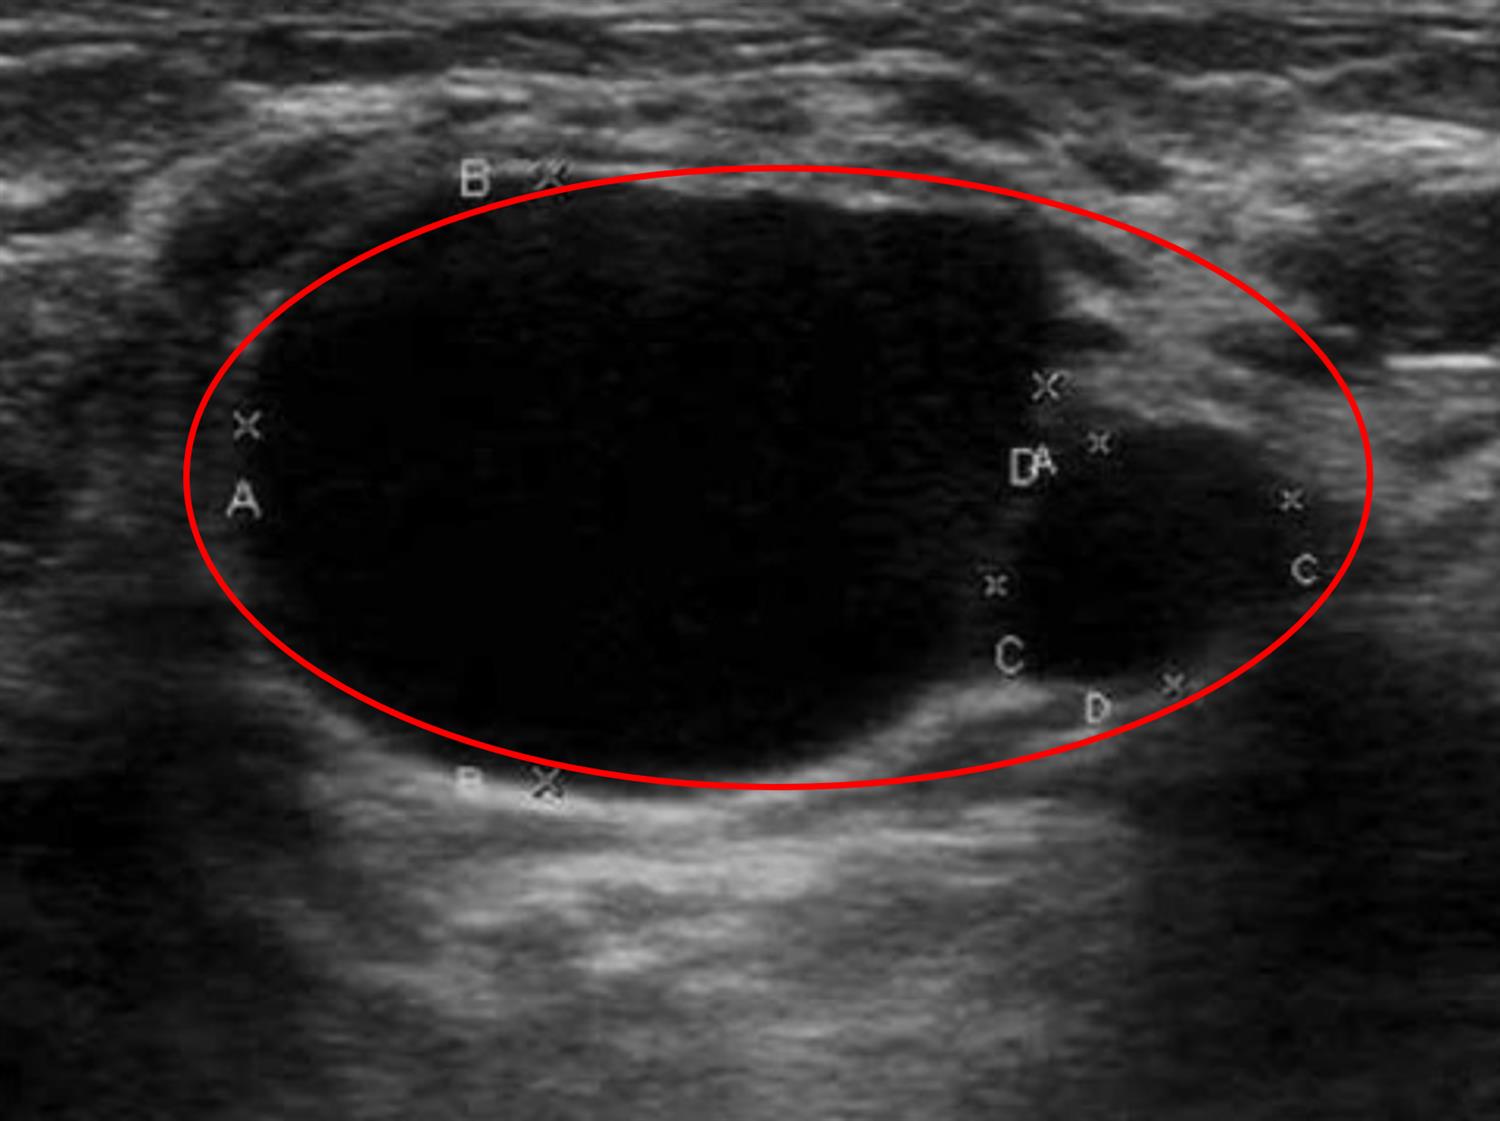

Figure/Illustration A is a sonographic image demonstrating a well-circumscribed, cystic structure that is anechoic (red circle). This finding is characteristically seen in the setting of a galactocele.

Galactoceles, or milk retention cysts, are common, benign breast masses that result from cystic collections of fluid. They are usually caused by an obstructed milk duct and present as periareolar, soft, cystic masses. These masses are most commonly detected after a woman ceases to breastfeed, but they may also occur anytime from the last trimester of pregnancy through the beginning of lactation. Diagnosis is often based on clinical information and imaging studies. On ultrasound, galactoceles appear as well-marginated, anechoic cysts. Sometimes galactoceles may exhibit internal echoes due to fatty milk material. Mammography is usually not indicated due to benign appearance on sonography, but if performed, this study may exhibit a classic fat-fluid level. Aspiration of the cyst, which yields a milky substance, confirms the diagnosis. Management is observation as there is no increased risk of subsequent breast cancer.

A 27-year-old woman presents to her obstetrician with a 1-week history of a new breast mass. She noticed the lump when she was trying on a new swimsuit at the store. She has never had a lump in that location before, and she denies any discharge, fever, or recent trauma to the area. She used to play soccer and says maybe a couple of soccer balls hit her in the chest years ago. She has a 5-month-old baby and is currently weaning from breastfeeding. She denies any family history of breast cancer. She has no other significant medical history and takes no medications. Her temperature is 97.0°F (36.1°C), blood pressure is 115/78 mmHg, pulse is 55/min, and respirations are 12/min. A chaperoned physical examination is notable for a periareolar, mobile, well-circumscribed, and nontender mass at the left breast. There are no overlying skin changes. An ultrasound study is performed as shown in Figure A. Which of the following is the most likely diagnosis?